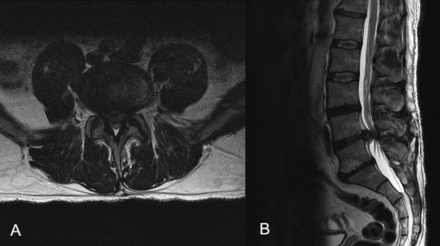

The images below are from just three of the many published case studies showing severe bulging discs in the neck and lower back that the nervous system was able to heal naturally:

Case Study 2: